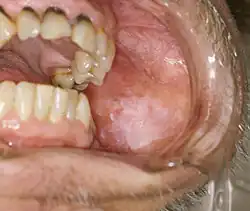

Mouth

Oral lichen planus (also termed oral mucosal lichen planus), is a form of mucosal lichen planus, where lichen planus involves the oral mucosa, the lining of the mouth.[39] This may occur in combination with other variants of lichen planus. Six clinical forms of oral lichen planus (OLP) are recognized:[40]

- Reticular

- The most common presentation of oral lichen planus (OLP) is characterised by the net-like or spider web-like appearance of lacy white lines, known as Wickham's striae.[41] This is usually asymptomatic. Reticular OLP may progress to the more severe subtypes, such as the erosive form, if left untreated.[2]

These types often coexist in the same individual. Oral lichen planus (OLP) tends to present bilaterally as mostly white lesions on the inner cheek,[41] although any mucosal site in the mouth may be involved. Other sites, in decreasing order of frequency, may include the tongue, lips, gingivae, floor of the mouth, and very rarely, the palate.[41]